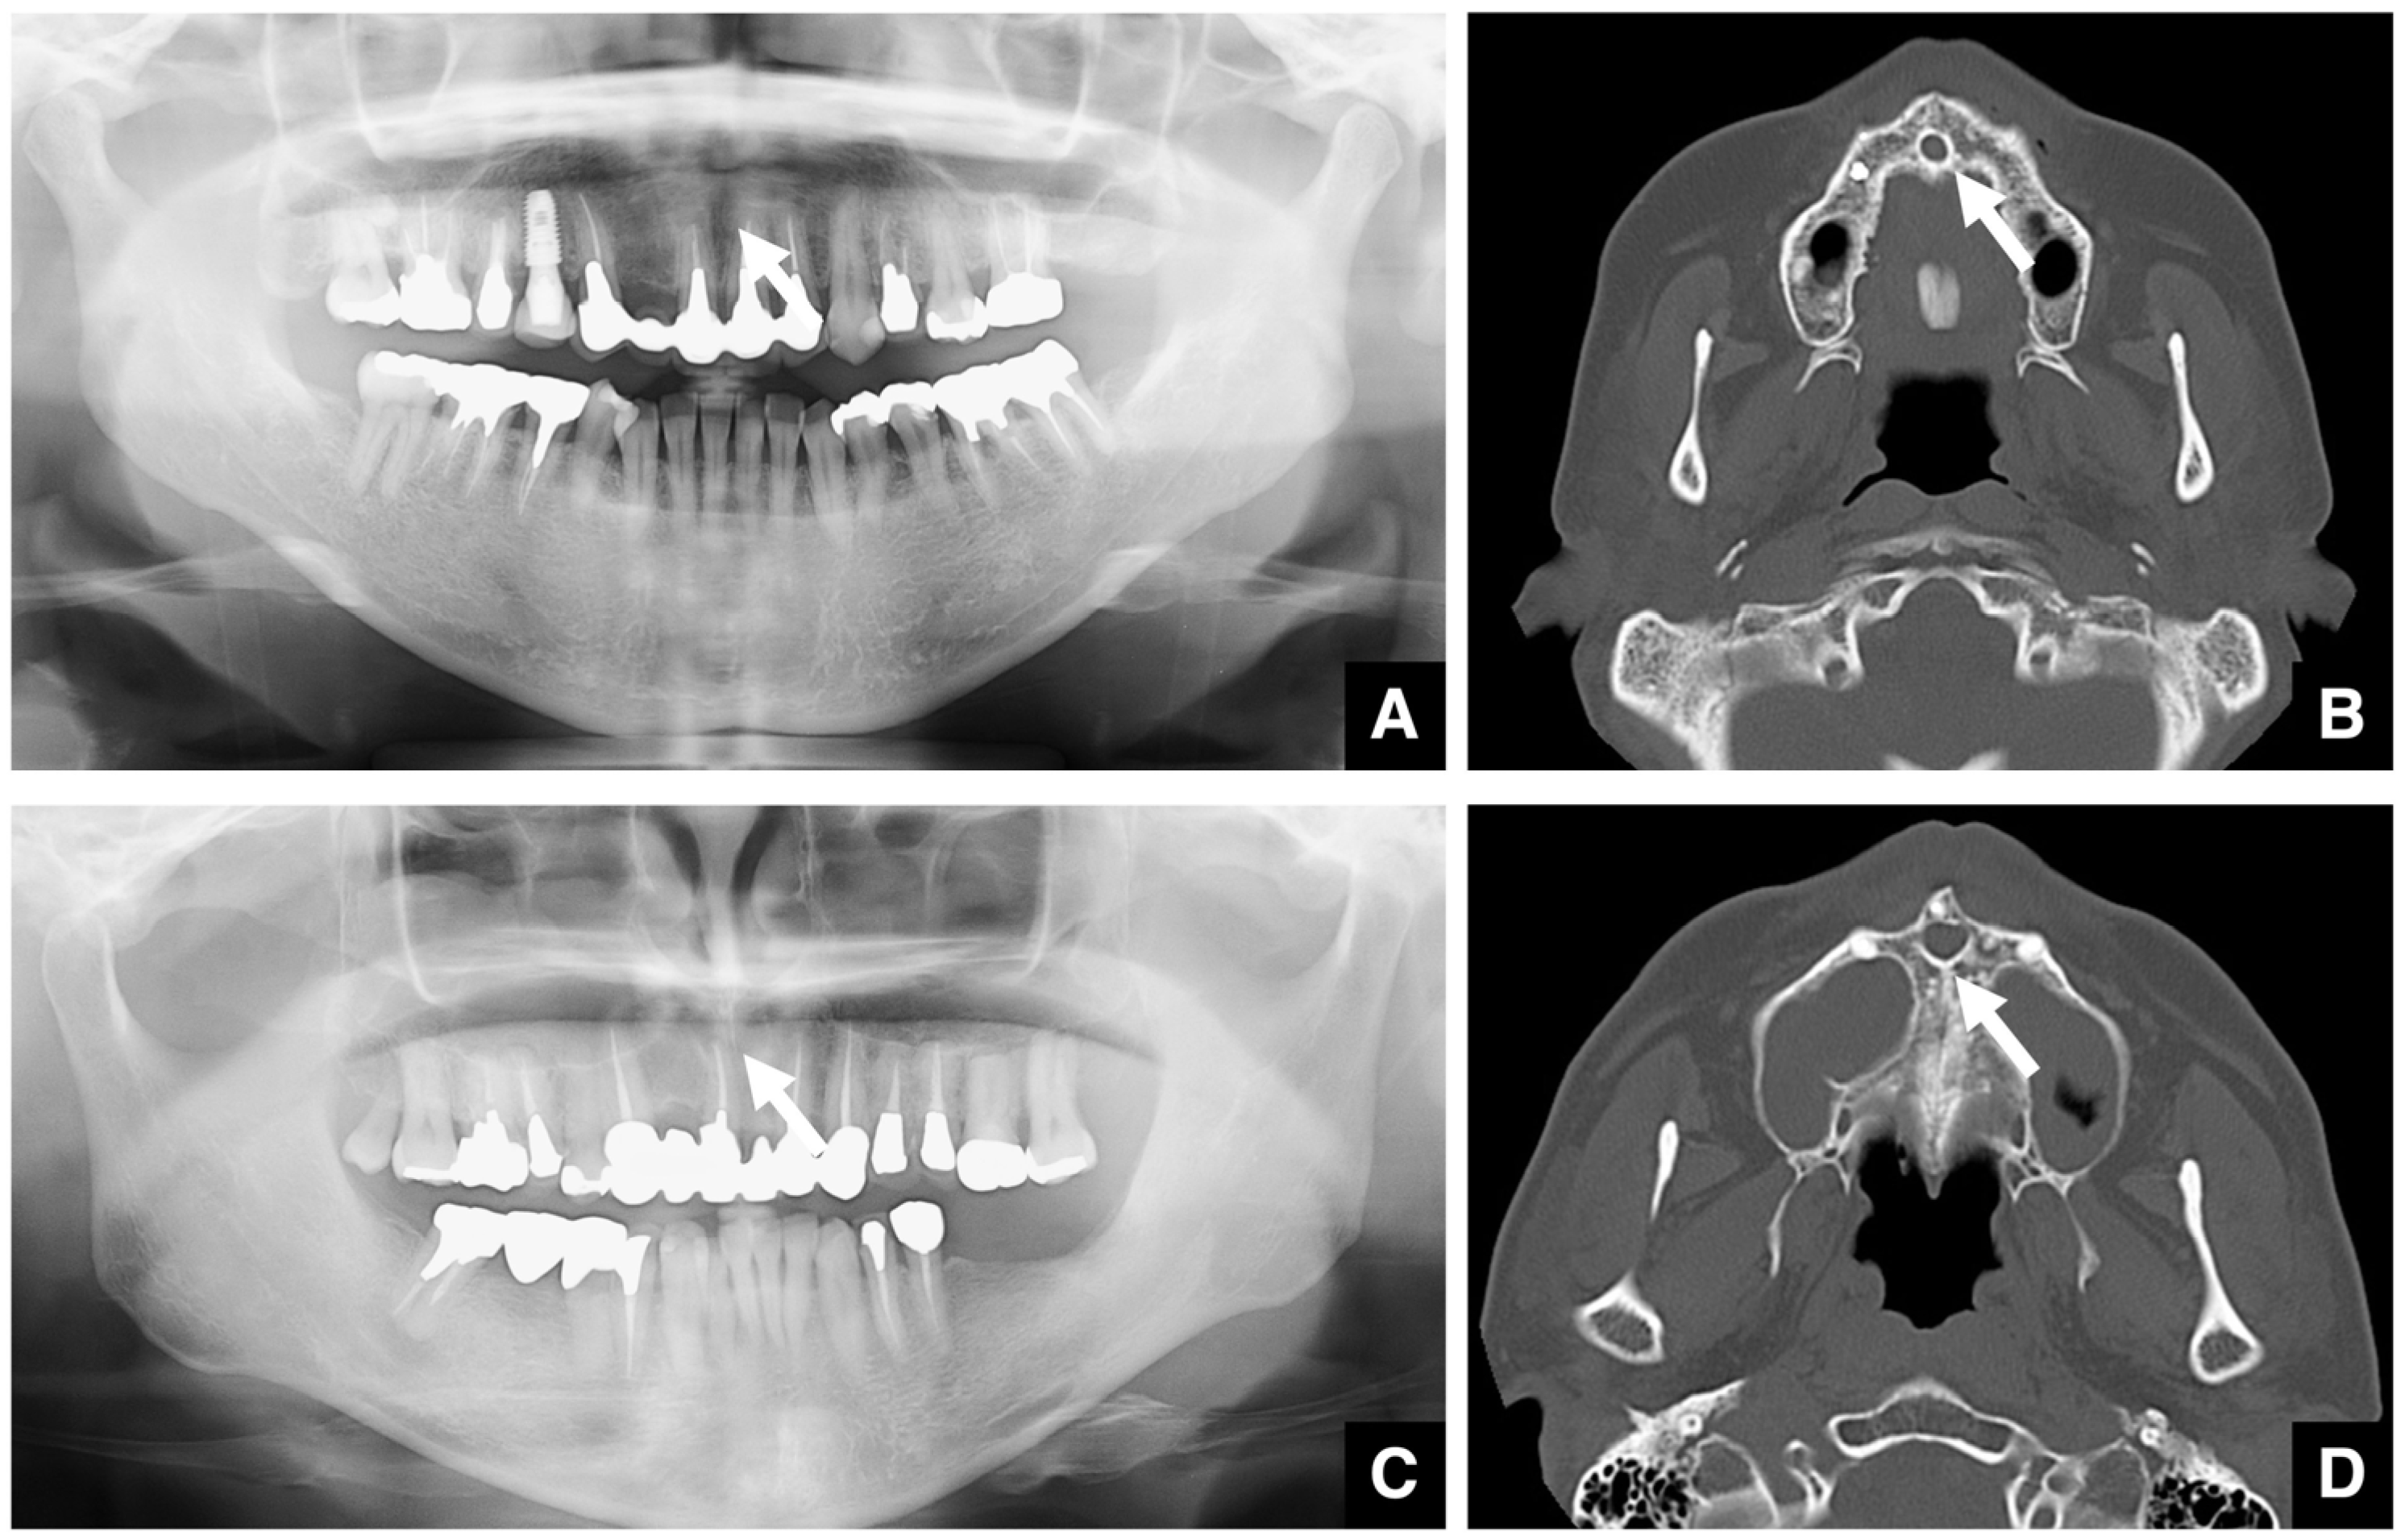

| Enhanced safety through improved visibility 1. Course of the submental artery and its branches Identification of the submandibular gland and its medial aspect 2. Course of the sublingual artery and the mental nerve Identification of the mentalis muscle, hyoglossus muscle, and anterior belly of the digastric muscle and their medial aspects (Observed within the fatty tissue beneath the chin) 3. Course of small blood vessels along the bone surface Degree of looping at the mentum foramen during opening, course of the incisive branch Setting the osteotomy line 1. Position of the mental foramen and course of the incisive branch Record the position of each root for each lower tooth 2. Position of the mandibular anterior tooth roots Record the thickness of the cortical bone using the mandibular teeth as a reference point 3. Variation in cortical bone thickness in the anterior mandible Depression of the cortical bone in the mandibular anterior region, trabecular bone defect |